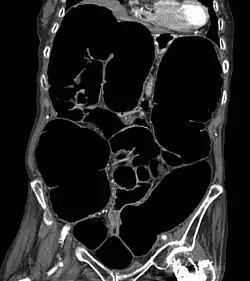

CT-Scan showing a coronal section of the abdomen of an elderly lady with an IPO.

The symptoms of IPO are nonspecific. It is not unusual for patients to present repeatedly and to undergo numerous tests.[4] Mechanical causes of intestinal obstruction must be excluded to reach a diagnosis of pseudo-obstruction. Attempts must also be made to determine whether the IPO is the result of a primary or secondary condition.[15] A diagnostic work-up may include:[14]